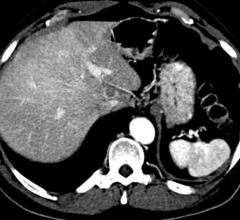

Today, perfusion MRI is primarily applied when diagnosing strokes and tumors. It measures which brain areas receive insufficient blood supply after a stroke occurs. It can also assess the viability and functionality of the liver and kidneys. Furthermore, the method can visualize which regions of a tumor are supplied with the most blood. In these areas, the ulcer grows the fastest, but is also more receptive to therapeutic treatment – helpful information for radiation therapists.